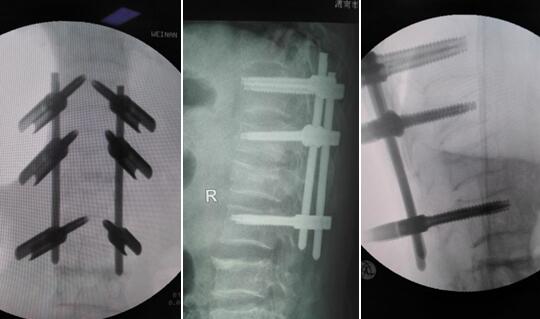

术中及术后X线片

术中C臂下进行操作